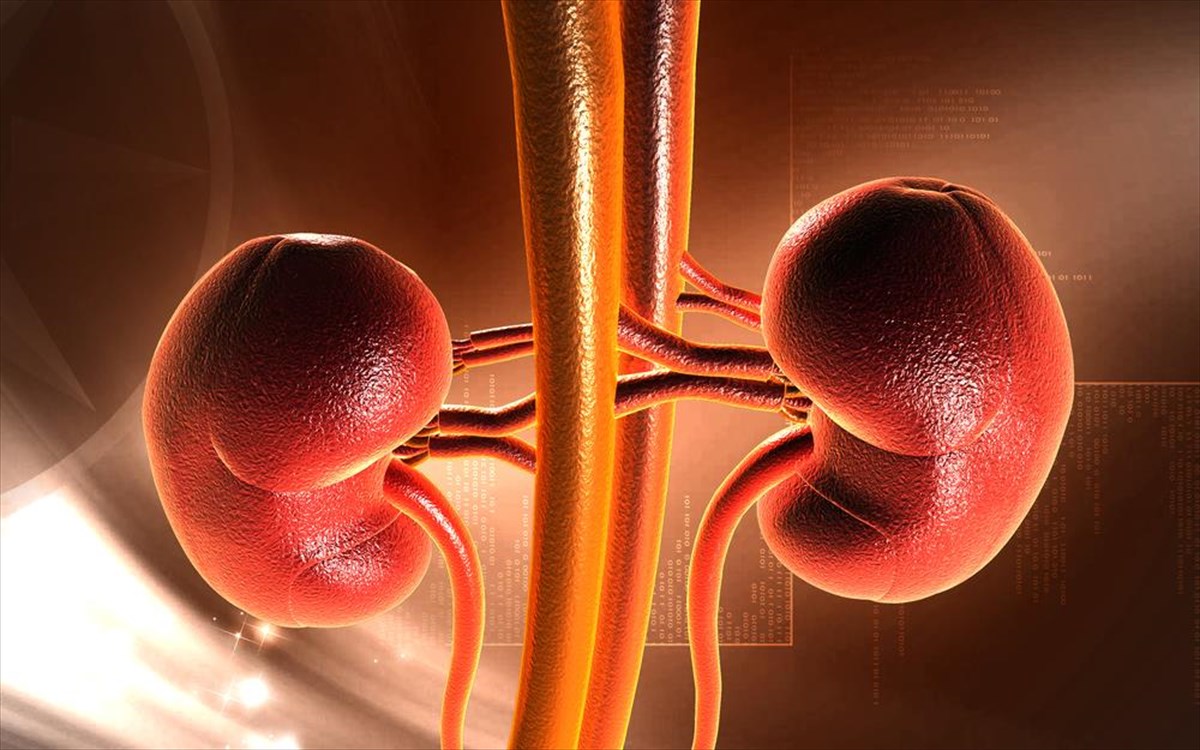

Όπως και στην περίπτωση των πνευμόνων, έτσι και με τα νεφρά, μπορούμε να ζήσουμε μόνο με το ένα.Σύμφωνα με το Εθνικό Ίδρυμα Νεφρού των ΗΠΑ, τα προβλήματα που μπορεί να εμφανιστούν είναι η ελαφρά μείωση στη νεφρική λειτουργία και η υψηλή αρτηριακή πίεση. Αν μάλιστα δεν αντιμετωπίσετε επιπλοκές όπως νεφρική νόσο, τότε πιθανόν να μην χρειαστεί να αλλάξετε την διατροφή σας.